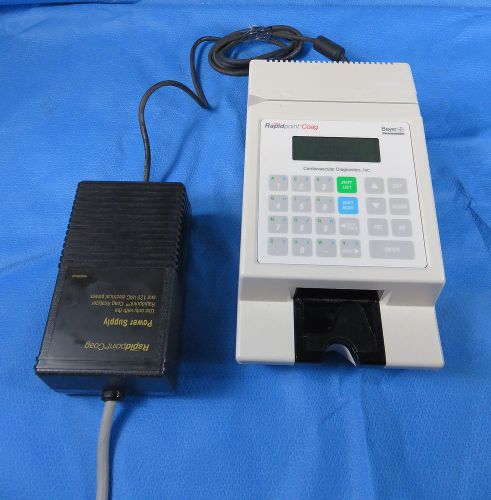

Bayer Rapidpoint Coag Coagulation Blood Analyzer w/ Power Supply